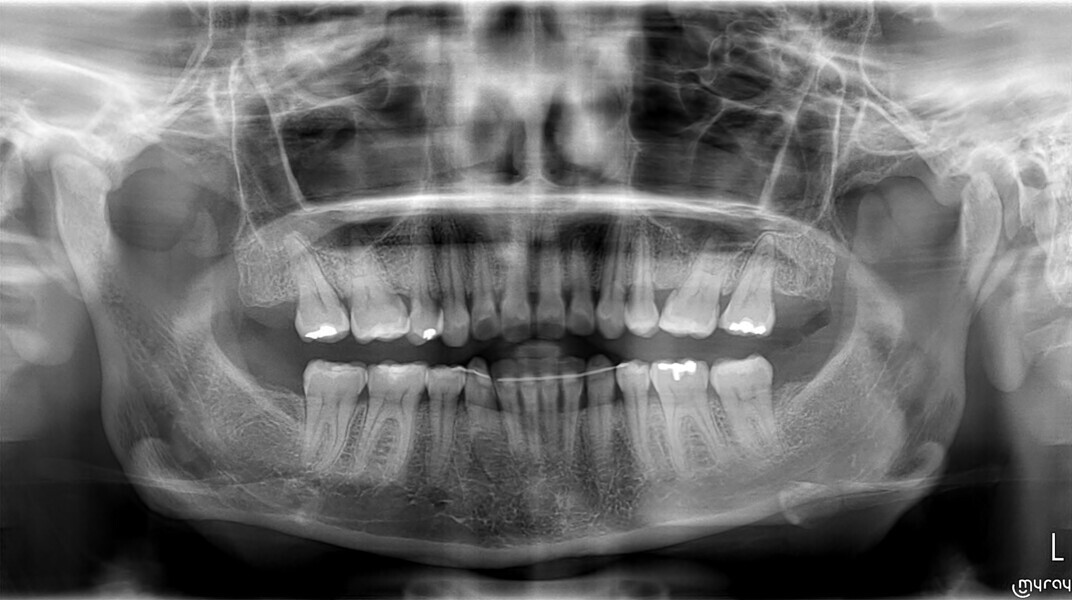

Before the aligner treatment began, the maxillary and mandibular second premolars were extracted to create space. With orthodontic treatment, distalisation of the anterior teeth was achieved by employing maximum mandibular anchorage and moderate maxillary anchorage (Figs. 5–7). At the end of the treatment, a stable bilateral Class I occlusion had been achieved, as well as normal inclination and retrusion of the anterior teeth, consequently improving the profile (Figs. 8–10).

Among the post-treatment recommendations was a mouth guard, which the patient was advised to wear every night to protect the teeth from the excessive occlusal force of bruxism.